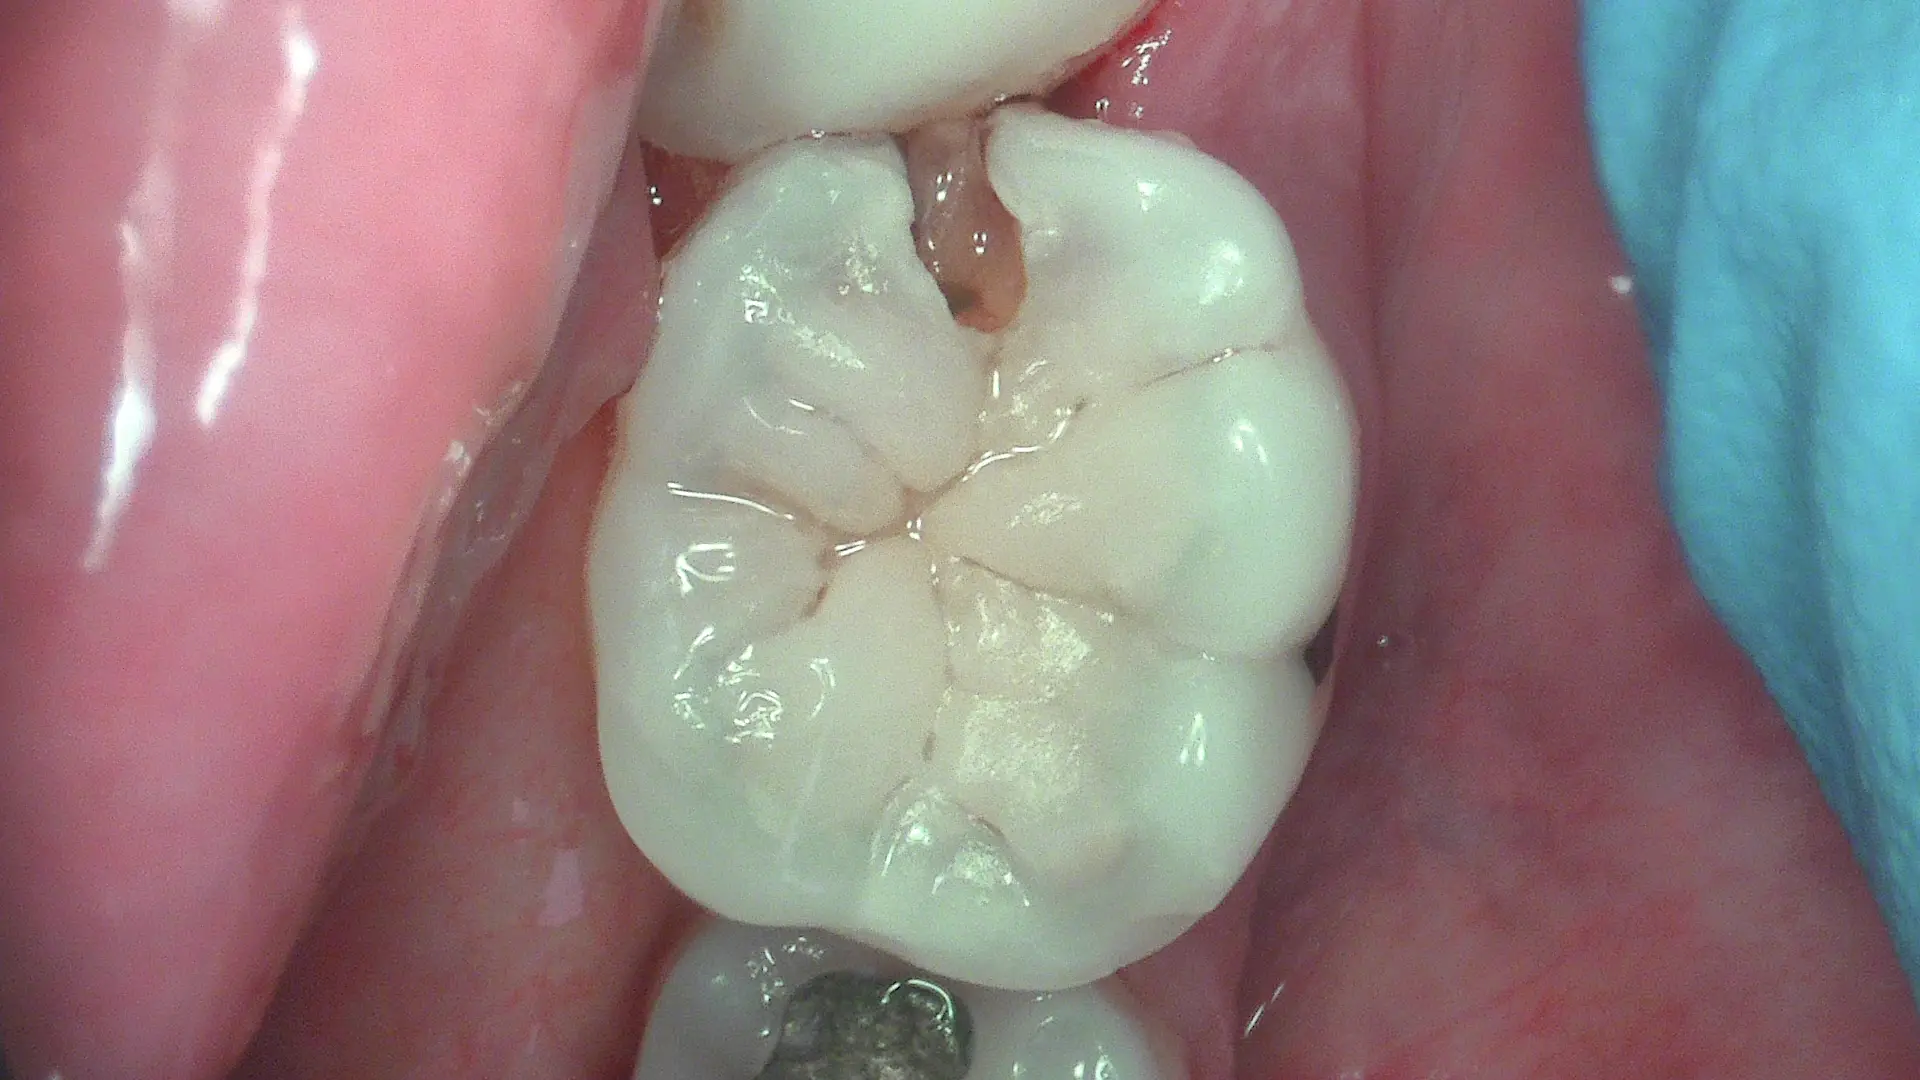

True-Colour Clinical Photography

Full HD white-light mode for standard clinical images — restorations, fractures, gingival condition and patient communication. Sharp, true colour at 1920×1080.

Crack & Fracture Identification

Near-infrared transillumination makes tooth cracks and proximal caries visible without X-ray exposure — essential for diagnosing cracked tooth syndrome with confidence.

Experience the exceptional Full HD detail and fluorescence diagnostics in real patient cases — from early caries detection to minimally invasive restorations.